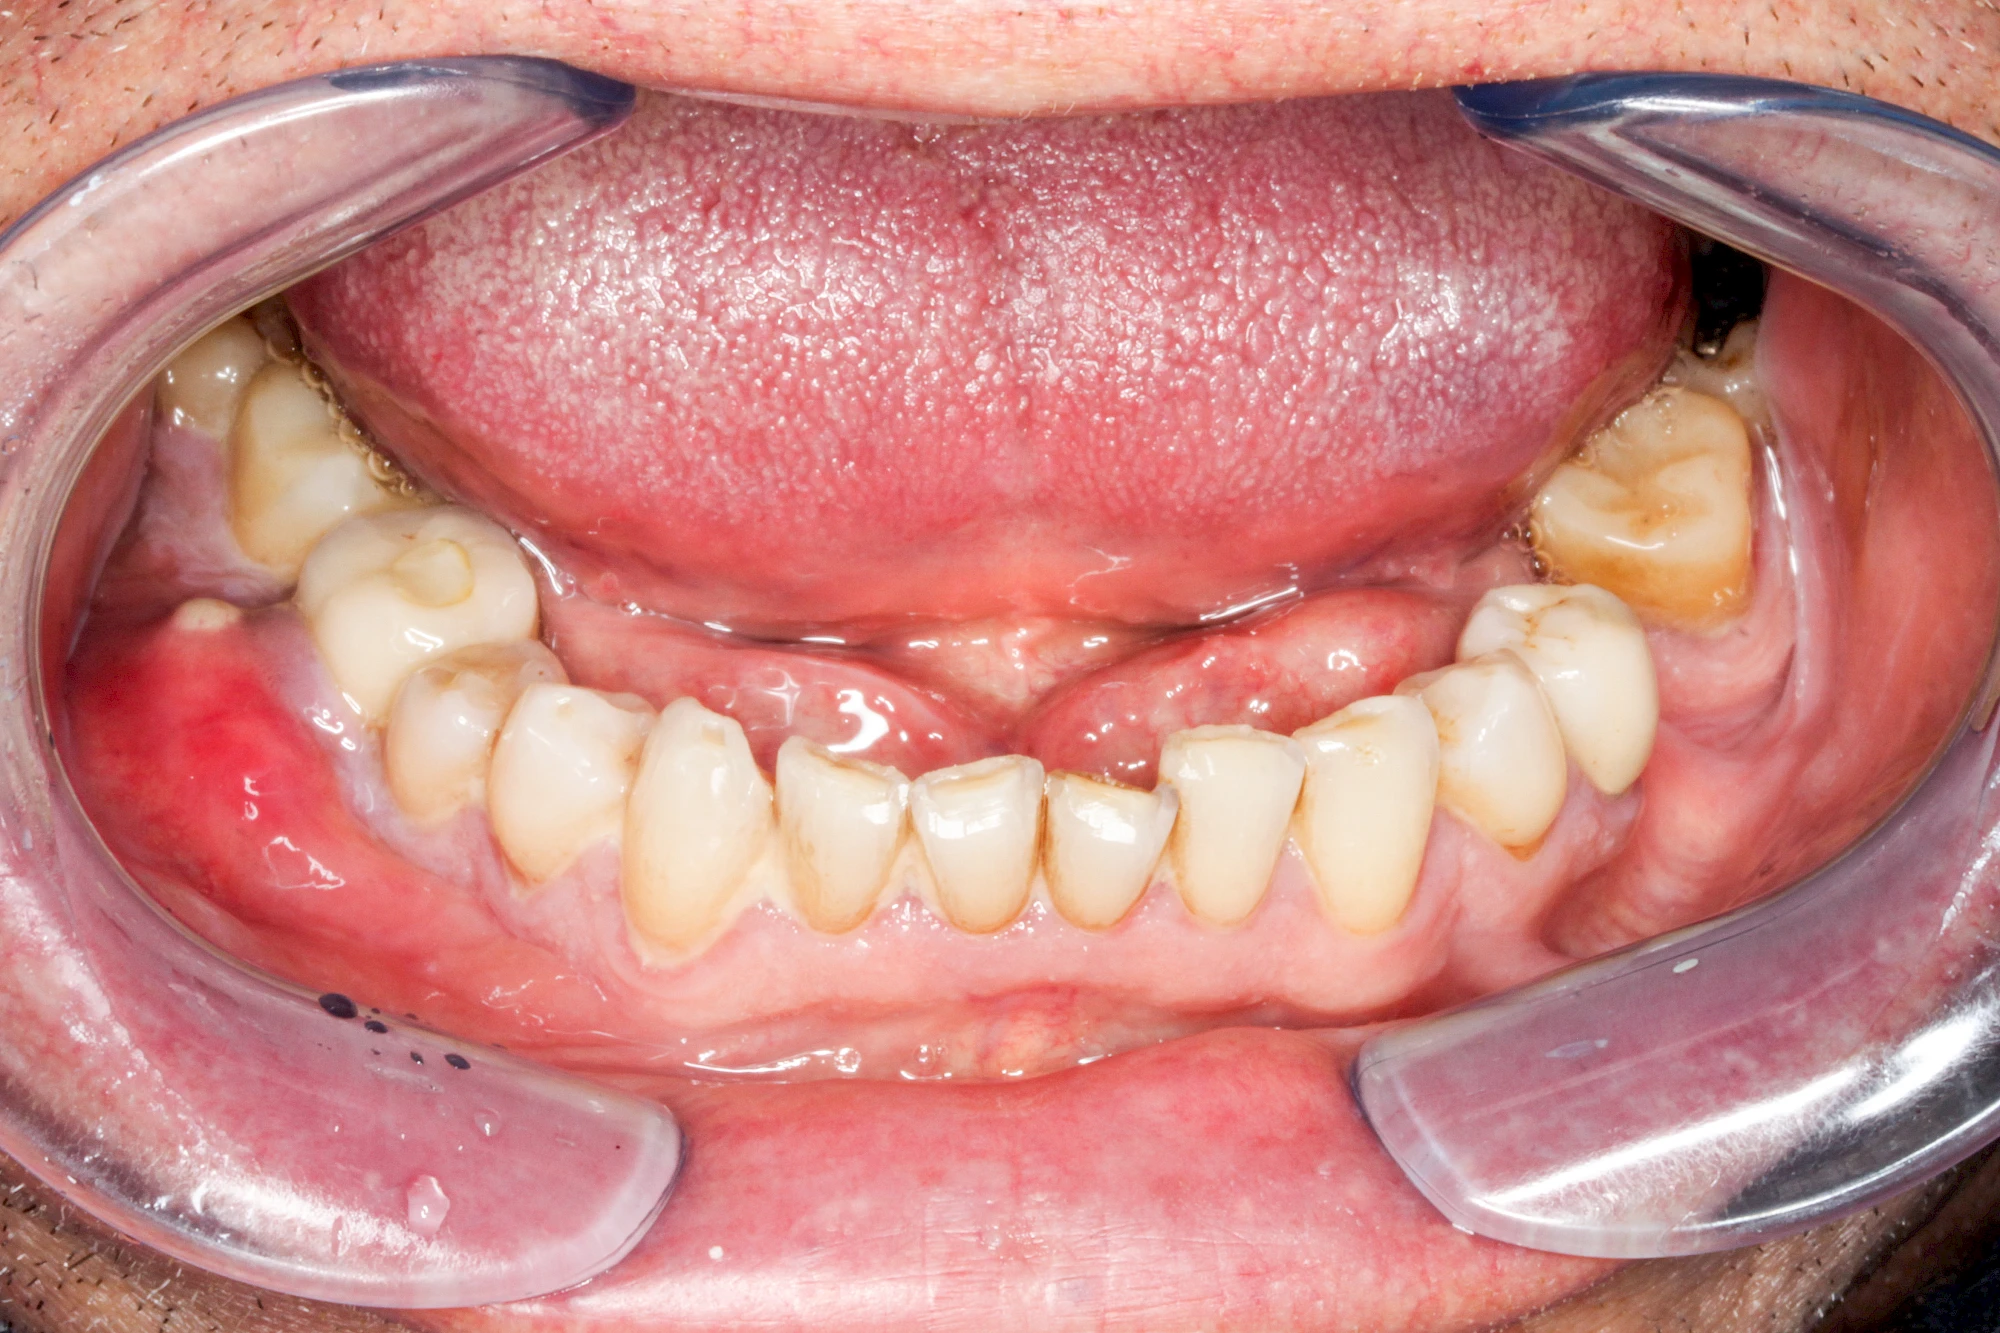

Ist zunächst nur das Zahnfleisch von der Entzündung betroffen, spricht man von Gingivitis. Später, wenn auch der Knochen um die Zähne herum entzündet ist, spricht man von einer Parodontitis. Bei der Parodontitis wird der Knochen nach und nach abgebaut und das Zahnfleisch zieht sich zurück. Die Zahnhälse und Zahnwurzeloberflächen liegen mehr und mehr frei. Die Zähne werden zunehmend lockerer und fallen schließlich aus.